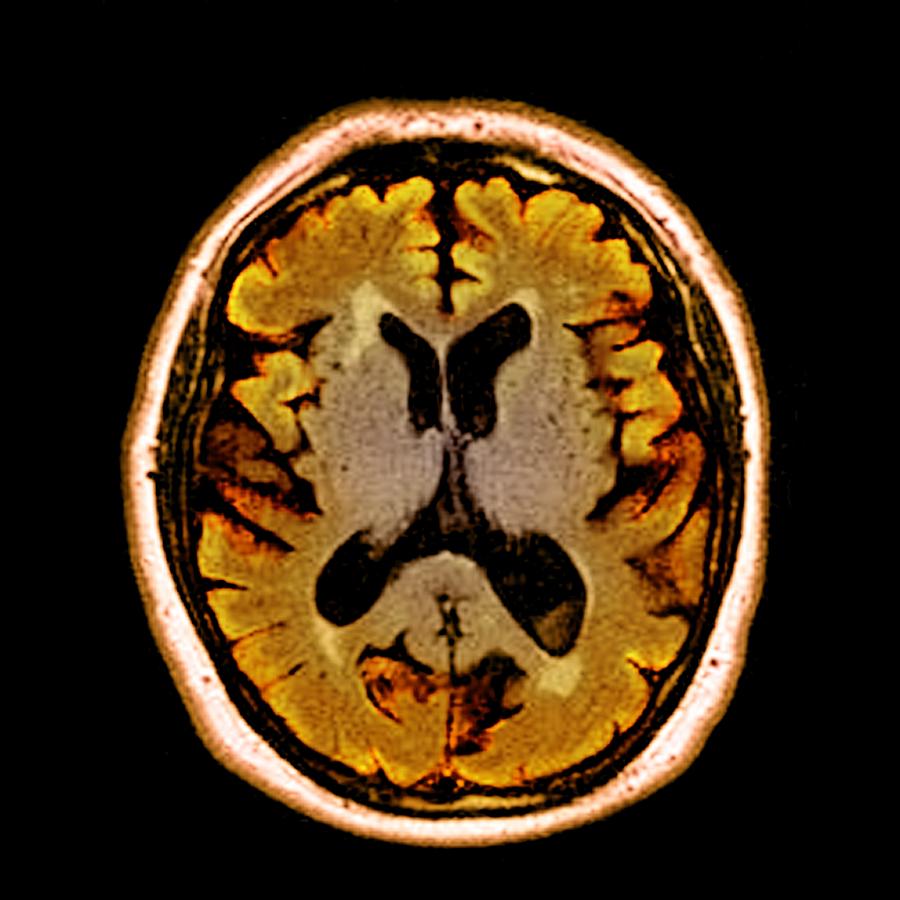

Alcoholic Dementia, Mri Scan Photograph by Du Cane Medical Imaging Ltd

Alcoholic Dementia, Mri Scan Photograph by Du Cane Medical Imaging Ltd

Alcoholic Dementia, Mri Scan Photograph by Du Cane Medical Imaging Ltd

Dementia, MRI scans – Stock Image – M140/0433 – Science Photo Library